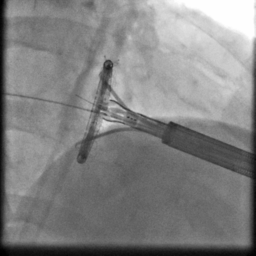

手术过程造影

手术在厦心杂交手术室进行,患者处于全麻状态,在实时三维食道超声的指引下,心外科在患者左胸前切开4-5cm的切口,经心尖预缝荷包区域导入AMEND成形环植入系统,顺利通过二尖瓣结构中央区域进入左心房后,在体外操作AMEND系统将“D”型成型环在主动脉瓣与二尖瓣间极为狭小的空间内精确释放,并先后铆钉二尖瓣环的后叶及前叶,从而达到缩小二尖瓣环的目的(图2),这一步操作要求非常精准,稍有不慎便会损伤周围组织,引起并发症。术后即刻,患者二尖瓣反流明显减轻,达到轻度水平(图3),手术从麻醉到结束平均历时3个小时。